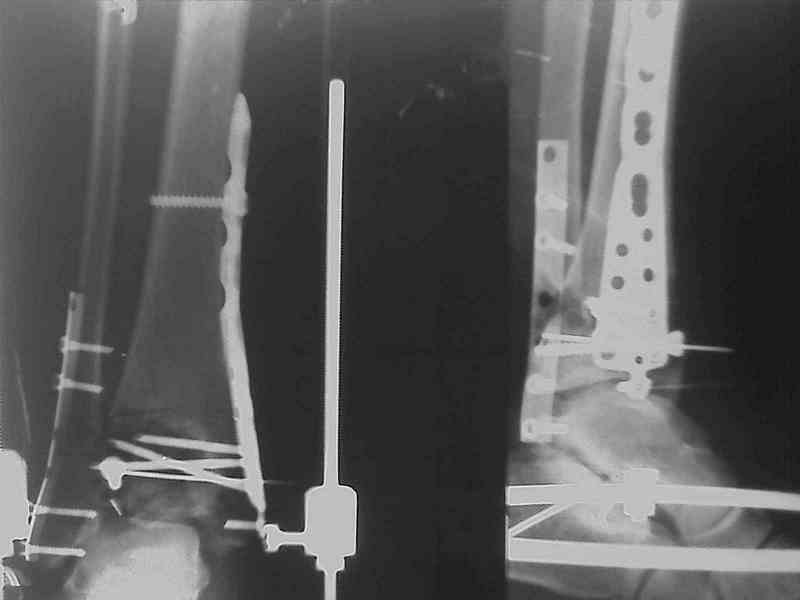

Снова приветствую вас, коллеги. К моменту вступления в обсуждение аксакалов, операция была, увы, выполнена(31.10.07.) Начали с доступа к наружной лодыжке, произвели ее фиксацию спицами, развернули кусок заднего края, наложили дистрактор, затем произвели дистракцию, фиксацию спицами дистального эпиметафиза б/бк,Рентгено-контроль. синтез наружной лодыжки 1/3пластиной. из двух коротких разрезов сформирован канал под медиальную тибиальную пластину LCP. Края ран ушиты без натяжения. Прочувствовать жесткость фиксации винтами с угловой стабильностью не удалось, поэтому дистрактор оставлен на энное время.

На представленных R-снимках не окончательный вид после остеосинтеза. Дистальная опора давила на стопу, пришлось ее сместить проксимально, в рез-те чего, она закрыла щель сустава, последние снимки не информативны.